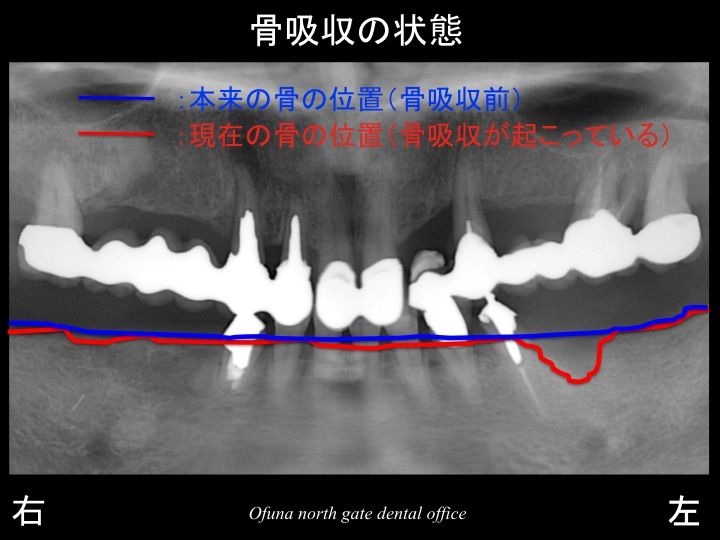

インプラントの治療計画を立てる前に

いつものように 骨吸収の状態を分かりやすくするために

下顎の 骨吸収の状態を線で書いたのが以下のレントゲンになります。

青線が骨吸収を起こす前の骨の位置です。

赤線は、現在の骨の位置です。

下顎左側の歯根破折 を起こしていた部位では、骨吸収が起こっています。